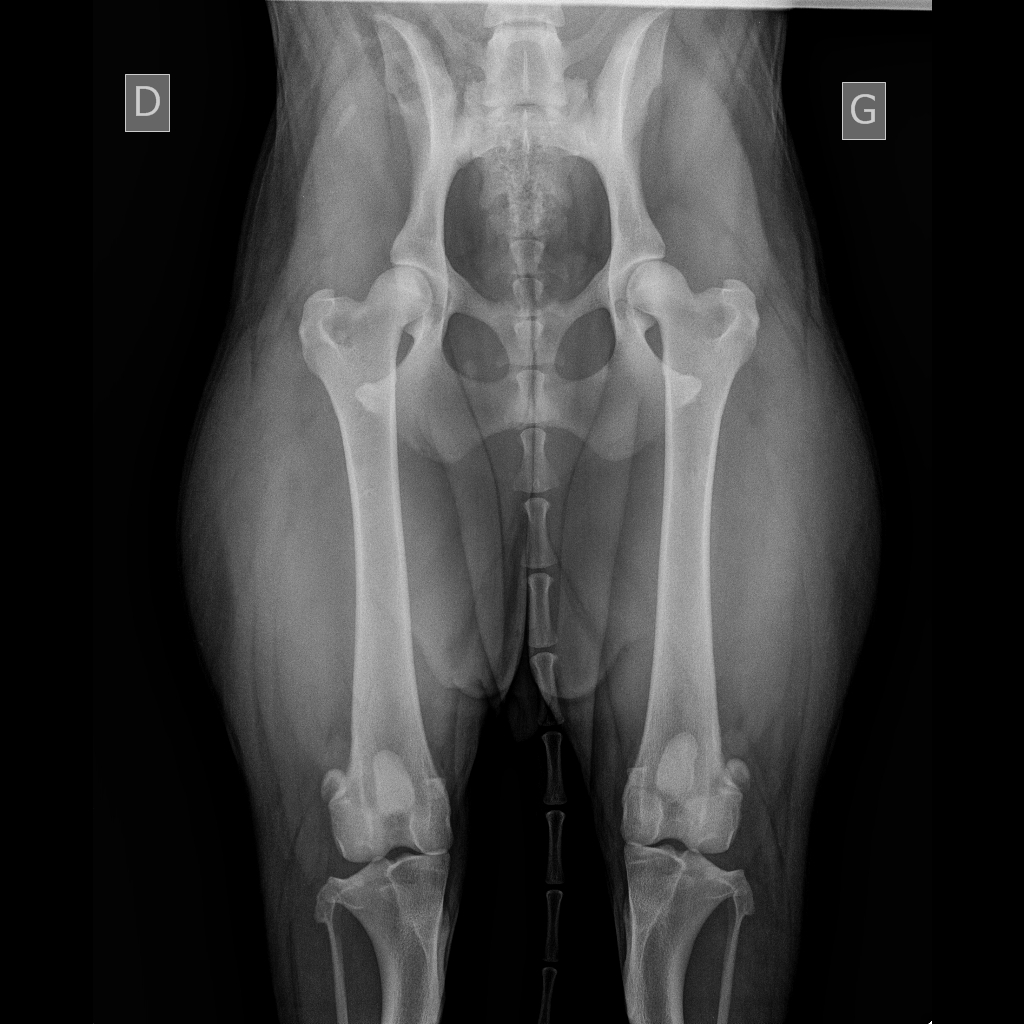

Télécharger radio eragone d'ainhoa

radio eragone d'ainhoa

radio des hanches de era qui sont très très bonnes